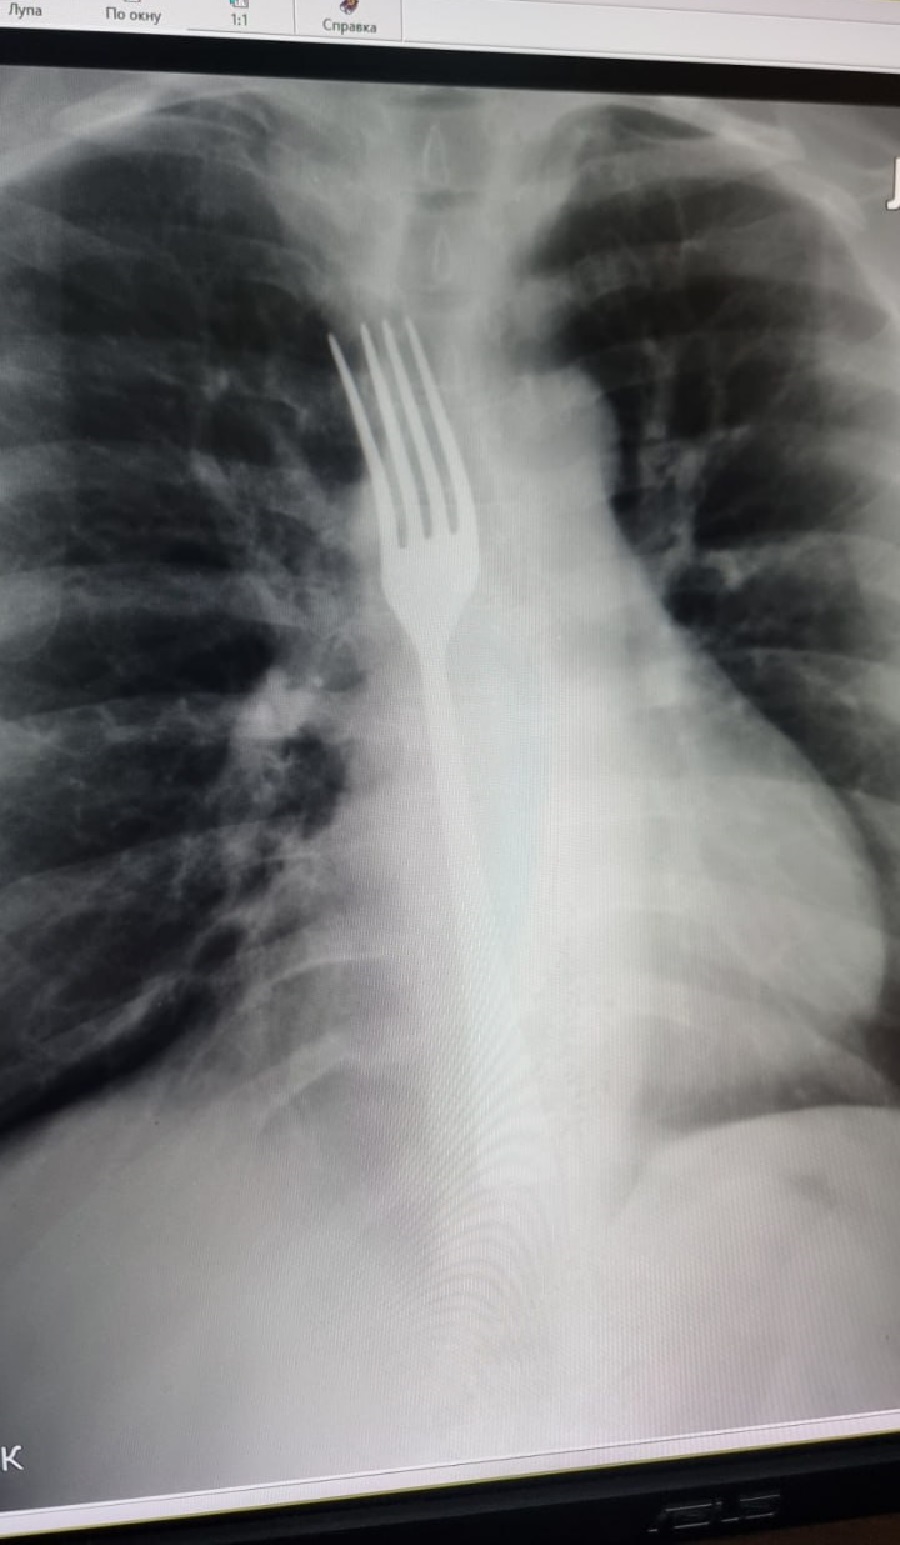

По информации медиков, женщина решила вызвать рвоту при помощи черенка вилки. После нескольких движений столовый предмет застрял в пищеводе. Пришлось вызывать скорую помощь.

Пациентку экстренно доставили в больницу. После обследования ее направили в операционную.

Женщине под наркозом частично опустили вилку в желудок, затем разрезали брюшную стенку, чтобы достать инородный предмет.